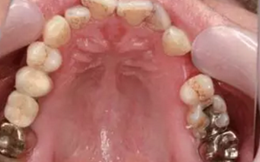

從圖1可以看出患者缺牙區(qū)的間隙充足,牙齦健康,頰側(cè)軟組織略有凹陷。

圖1 缺牙區(qū)的頰側(cè)和口內(nèi)照片